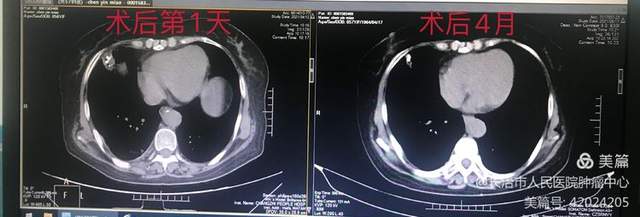

1.陈某,肺癌,肺粒子植入。粒子植入术前后对比,病灶PR